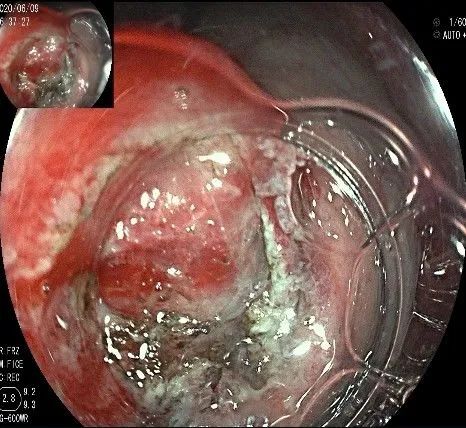

此时瘤体基底部已暴露出来,起源于固有肌层。

这是最后的“根”部。

换用IT刀可以轻松剥离,又避免切入过深造成穿孔。